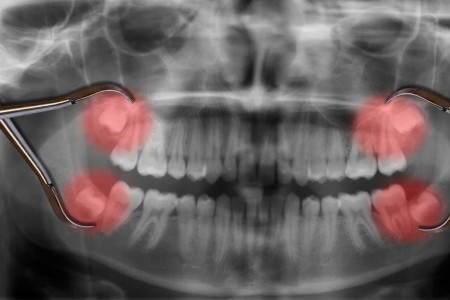

Can Wisdom Teeth Cause a Headache?

Read More

Do Wisdom Teeth Have To Be Removed?